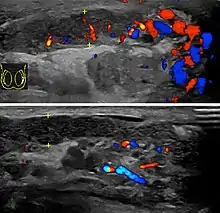

At ultrasound, the findings of acute epididymitis include an enlarged hypoechoic or hyperechoic (presumably secondary to hemorrhage) epididymis [Fig. 20a]. Other signs of inflammation such as increased vascularity, reactive hydrocele, pyocele and scrotal wall thickening may also be present. Testicular involvement is confirmed by the presence of testicular enlargement and an inhomogeneous echotexture. Hypervascularity on color Doppler images [Fig. 20b] is a well-established diagnostic criterion and may be the only imaging finding of epididymo-orchitis in some men.

Doppler ultrasound of epididymitis, seen as a substantial increase in blood flow in the left epididymis (top image), while it is normal in the right (bottom image). The thickness of the epididymis (between yellow crosses) is only slightly increased (7 mm).

Doppler ultrasound of epididymitis, seen as a substantial increase in blood flow in the left epididymis (top image), while it is normal in the right (bottom image). The thickness of the epididymis (between yellow crosses) is only slightly increased (7 mm). Doppler ultrasound of the scrotum of the same case, in the axial plane, showing orchitis (as part of epididymo-orchitis) as hypoechogenic and slightly heterogenic left testicular tissue (right in image), with an increased blood flow. There is also swelling of peritesticular tissue.

Doppler ultrasound of the scrotum of the same case, in the axial plane, showing orchitis (as part of epididymo-orchitis) as hypoechogenic and slightly heterogenic left testicular tissue (right in image), with an increased blood flow. There is also swelling of peritesticular tissue.